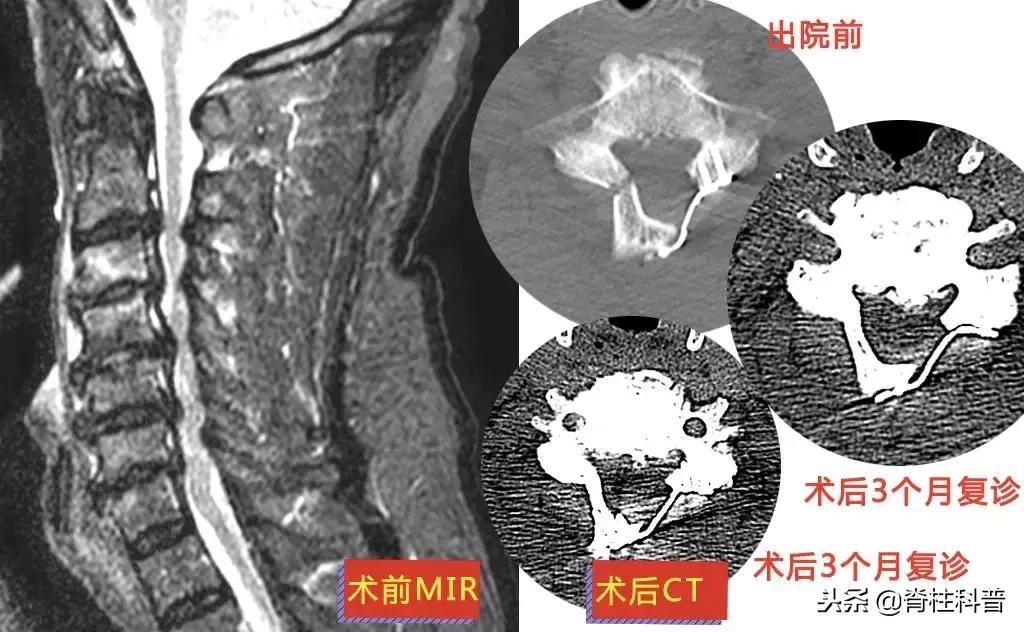

▲ 方大爷:脊髓型颈椎病

11月26日,在张主任的门诊,廖四爷回来复诊。情况还不错,上肢刀割样的疼痛已经消失,照了CT内固定也长得很好,但是萎缩的手臂还没得到恢复,还需要接受康复治疗。